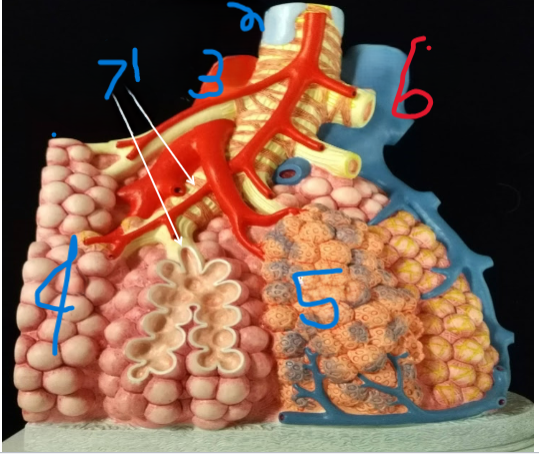

Terminal Bronchiole

What is depicted by #1

Bronchiole with smooth muscle

What is depicted by #2

Pulmonary vein, branch

What is depicted by #3

Alveoli

What is depicted by #4

Pulmonary capillaries

What is depicted by #5

Pulmonary artery, branch

What is depicted by #6

Respiratory Bronchiole

What is depicted by #7